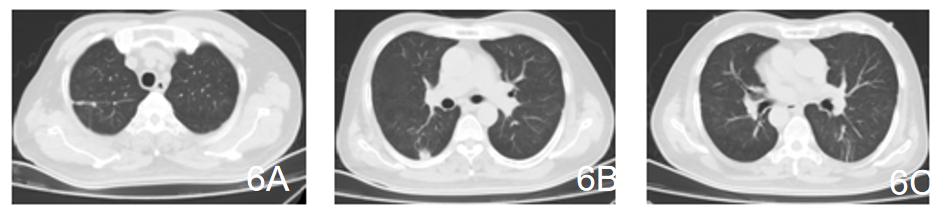

【图6】5月7日CT